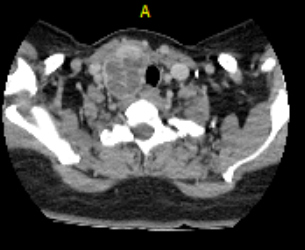

Se trata de una paciente de sexo femenino de 46 años con presencia de masa en hemicuello derecho asociada a disfagia mixta, emesis de contenido alimentario, odinofagia y pérdida de peso desde hace 1 año. Se realizaron estudios bioquímicos con hallazgo de hipercalcemia severa (17.2 mg/dl), PHT elevada y fósforo sérico normal. Se planteó diagnóstico de hiperparatiroidismo primario, solicitándose TC de cuello con hallazgo de masa de densidad heterogénea en relación al lóbulo tiroideo derecho asociada a adenopatías en el nivel VI, IIA bilaterales y IB a derecha (Figs. 1 y 2).